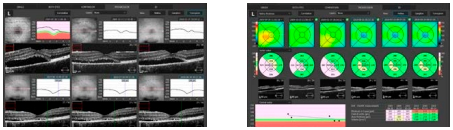

Наблюдение

Встроенная высокоточная функция сканирования и различение системы кровеносных сосудов Revo дает возможность проводить качественное сравнение релевантных и прошедших сканированных изображений. Специалист получает возможность наблюдать за переменами в морфологии и диагностировать смену тенденций прогрессирования.

Скан широкого поля обзора

Центрированное сканирование широкого поля обзора 12х12мм – это наилучший способ диагностики сетчатки пациента. Полноценное сканирование в томограммах с большим разрешением позволяет обнаружить практически все нежелательные трансформации на начальных стадиях. Периферийное сканирование дает возможность обнаружить болезни дальней периферии.